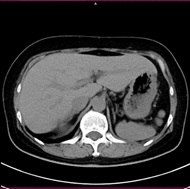

• 心臓CT(冠動脈CT)

当院の装置は管球1回転最速0.28秒と非常に早く、幅広い心拍の方に対応しています。

解析処理は専門のワークステーションを使用し、読影は循環器内科医師と画像診断専門医(遠隔画像診断支援)双方で行い、結果を循環器内科医師よりお伝えしています

心臓CT